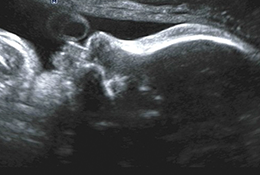

Com alta tecnologia realizamos diversos tipos de ultrassonografias: Obstétrica, Obstétrica com Doppler, Morfológica, 4D, Transvaginal, Transvaginal para pesquisa de Endometriose, Abdominal, Mamas, Tireoide e outros.